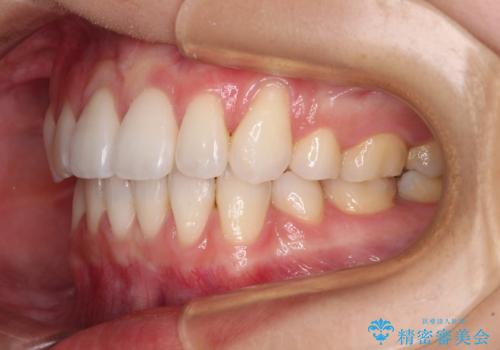

- 八重歯と口元の突出感を気にして来院された患者様です。

歯列が前方に突出しており、上下の正中がズレていたため、左側は上下第一小臼歯を、右側は上下第二小臼歯を抜去し、ワイヤー装置による矯正治療を行うこととしました。

当初はインビザラインによる矯正治療をご希望でしたが、正中を合わせたいことや、口元の突出感を改善したいことから、ワイヤー矯正を強く推奨しました。

治療期間は2年に満たず、スッキリとした口元に仕上がりました。